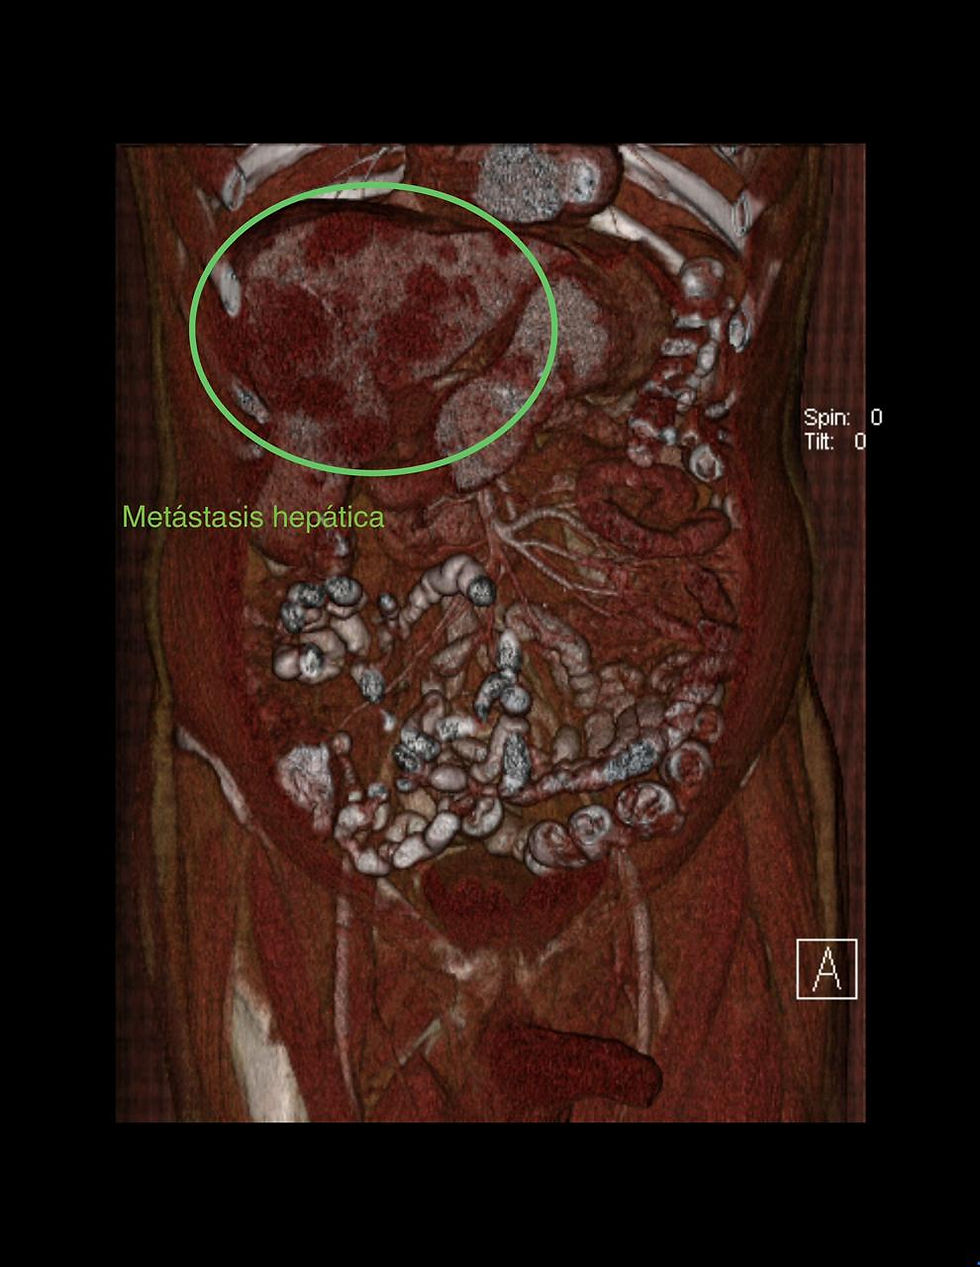

Una paciente joven acudió a consulta tras varios meses de presentar dolor en la región epigástrica. Estudios iniciales mostraron la presencia de lesiones focales hepáticas, lo que motivó la realización de una resonancia magnética con Primovist, un medio de contraste hepatobiliar diseñado para evaluar de forma más específica el tejido del hígado. Este contraste permite analizar tanto la vascularidad de las lesiones como su capacidad de captación en fases tardías, ofreciendo una caracterización mucho más precisa.

Con el uso de Primovist se observó que las lesiones hepáticas mostraban captación y retención del contraste en la fase hepatobiliar, un patrón típico de lesiones benignas como la hiperplasia nodular focal. Este comportamiento permitió diferenciarlas de lesiones potencialmente malignas, brindando un diagnóstico confiable y evitando procedimientos invasivos innecesarios.